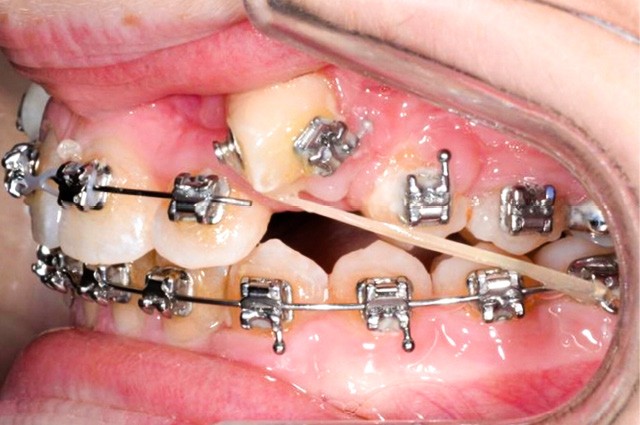

Trois jours plus tard, des bras en TMA .017 x .025 habillés d’une gaine de protection avec omega au contact des tubes des premières molaires et dont l’extrémité mésiale forme une boucle sont ligaturés aux dispositifs collés de traction.

Les maillons de la chaînette du dispositif de traction sont sectionnés progressivement de manière bilatérale à chaque rendez-vous à mesure que les canines sont déplacées en direction vestibulaire et le bras TMA est systématiquement religaturé au premier maillon transmuqueux avec une ligature métallique .010. L’ensemble est sécurisé par une goutte de composite fluide photopolymérisé.